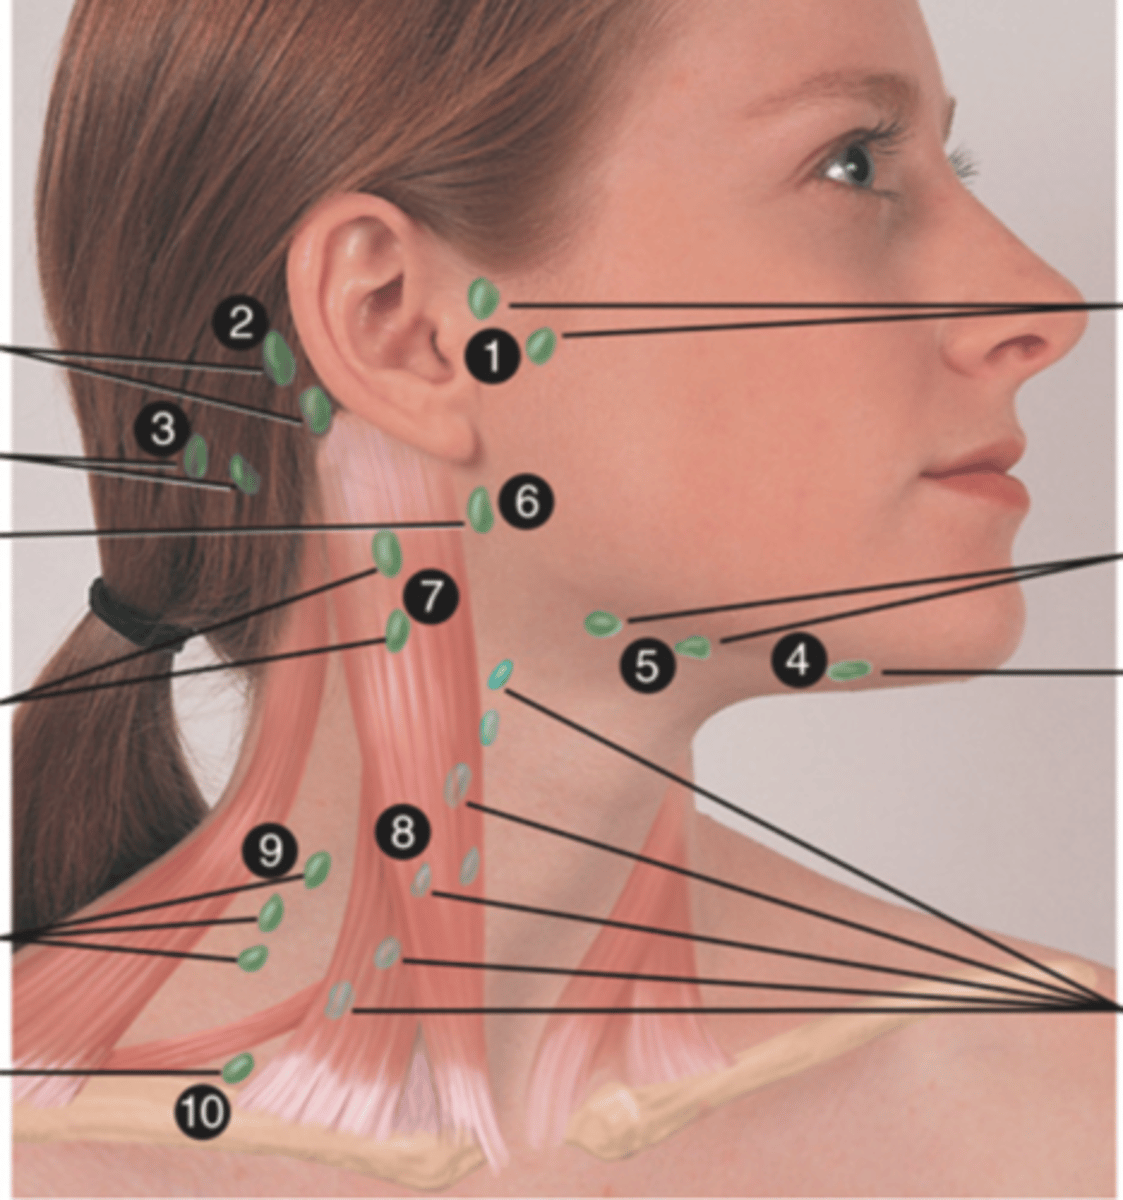

Major Lymph Nodes in the Neck (FUN!)

(Party People Often Sell Sardines Just So Dogs Pee Silver)

Preauricular Lymph Node

Lymph node in front of the ear (1)

Posterior Auricular Lymph Node

Lymph node behind the ear (2)

Occipital Lymph Node

Lymph node at the base of skull (3)

Submental Lymph Node

Lymph node under the chin (4)

Submandibular Lymph Node

Lymph node along base of mandible (5)

Jugulodigastric (Tonsil) Lymph Node

Lymph node under the angle of the mandible (6)

Superficial Cervical Lymph Node

Lymph node overlying the sternomastoid muscle (7); can feel enlarged even when there are no problems

Deep Cervical Chain Lymph Node

Lymph node located on the posterior triangle of the neck (8)

Posterior Cervical Lymph Node

Lymph node in the posterior triangle along the edge of the trapezius muscle (9)

Supraclavicular Lymph Node

Lymph node just above and behind the clavicle, at the sternomastoid muscle (10)